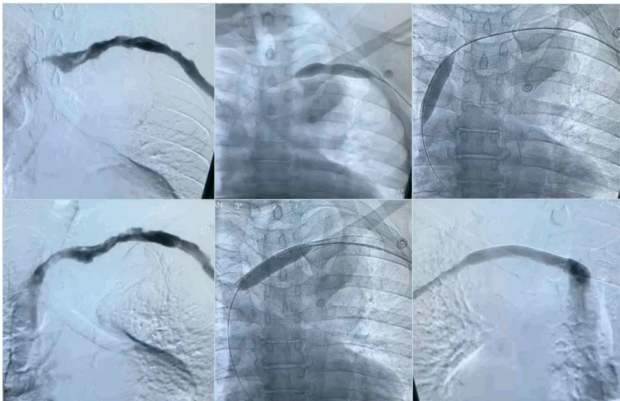

Postthrombotic VTOS represents the chronic phase, more than 3 months, following an axillary-subclavian vein thrombosis episode. In addition to the preexisting extrinsic compression impeding the venous outflow, it can also be associated with venous scarring that causes luminal narrowing related to the postthrombotic changes leaving residual synechiae on the inner venous wall. Patients usually present with a clear history of prior upper-limb deep vein thrombosis (DVT) for which they were treated with anticoagulation, or sometimes with no history of previous DVT and they present for the first time with venous insufficiency symptoms and signs (chronic limb swelling, heaviness, fatigue, bluish discoloration, prominent venous collaterals on the shoulder and the chest wall and reduced functional capacity). It should be noted that in some cases recanalization can mask the presence of significant luminal narrowing in resting position using DUS or even venography (Figure 3). However, with arm hyperabduction, it becomes clearly visible (Figure 4). Also doing a balloon test in these cases can help detect a masked venous stenosis (Figure 5).9

Figure 3. Venogram of arms in neutral position with postthrombotic syndrome (PTS) on the right side and no venographic signs of venous obstruction on the left side.

Figure 4. Venogram for arms in abduction position showing subclavian vein compression on both sides.

Figure 5. Balloon test for the right side with postthrombotic syndrome (PTS) with visible waist of the balloon denoting significant venous stenosis.